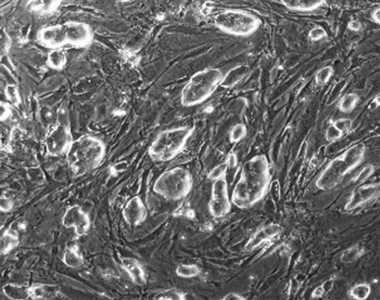

This handout photo released by The Whitehead Institute shows reprogrammed fibroblasts. Scientists have long hoped to bypass the embryo procedure, and simply reprogram ordinary body cells to behave like stem cells. Now three scientific teams say they've done that - at least in mice. [AP]